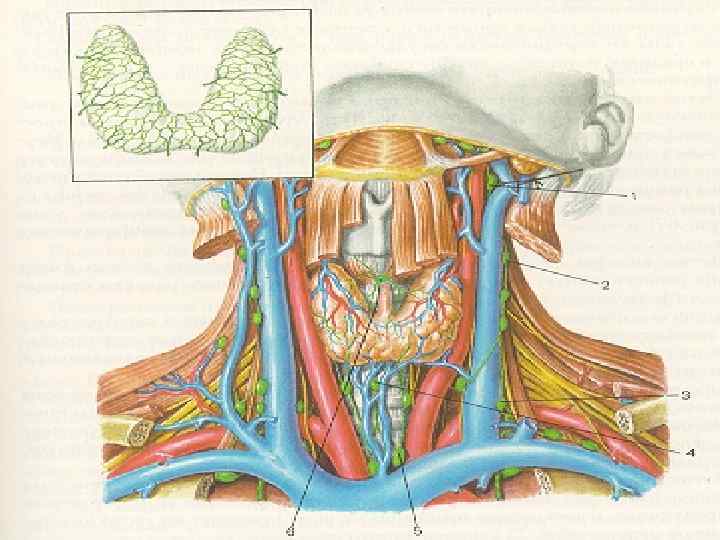

Методы исследования щитовидной железы 1 Клинико-физикальное обследование осмотр; ( деформация шеи, расширение вен шеи, одутловатость лица, пучеглазие) пальпация; (увеличение железы, выявление узлов) перкуссия; аускультация; измерение окружности шеи. II. Ларингоскопическое исследование III. Рентгенологическое исследование Пневмомедиастинум Пневмотиреография

Методы исследования щитовидной железы 1 Клинико-физикальное обследование осмотр; ( деформация шеи, расширение вен шеи, одутловатость лица, пучеглазие) пальпация; (увеличение железы, выявление узлов) перкуссия; аускультация; измерение окружности шеи. II. Ларингоскопическое исследование III. Рентгенологическое исследование Пневмомедиастинум Пневмотиреография